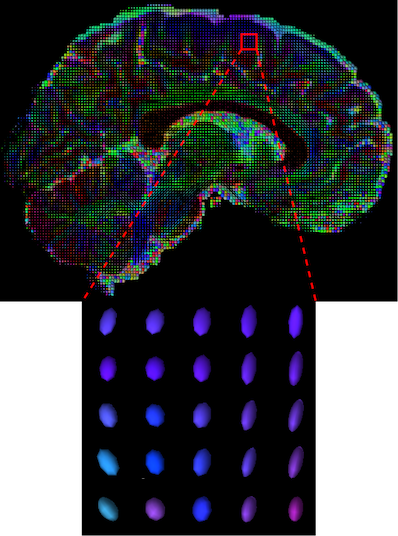

The visualization of inpainted results (showing the whole diffusion tensor for each voxel) generated from different models are demonstrated in Figure 3, where the tensor is represented in RGB coding that colours red, green and blue represent diffusion in the x, y, and z axes respectively. One typical example of reconstruction in the disrupted ROIs has been zoomed for visualization. Compared to the ground truth, TW-BAG is able to generate more distinct orientations following the original distribution and intensity across sagittal, coronal and axial views, which could demonstrate water diffusivity (denoted by eigenvalues of tensor model) more accurately. As indicated in Figure 4, the boundaries and textures of the FA map for TW-BAG are less blurry than the other competing models, validating the effectiveness of TW-BAG from a neuroscience perspective.